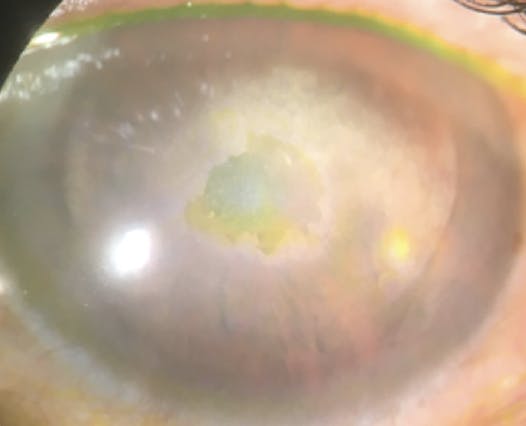

Band Keratopathy

Band keratopathy is a chronic degeneration of the corneal tissues characterized by whitish-gray opacities formed from calcium deposits in the subepithelium, Bowman layer, and the most anterior layer of the stroma (Figure 5).3 These deposits are mostly found in the intrapalpebral zone growing from the periphery to the central cornea.3

To treat band keratopathy, a Weck-cel surgical sponge (BVI) or diamond-tip burr can be used to gently debride the overlying loose epithelium. Calcium removal is facilitated by continuously placing fresh ethylenediaminetetraacetic acid on the surface to chelate with the calcium and remove it from the epithelium. Occasionally, patients may have concomitant corneal scarring that would benefit from gentle diamond-tip burr polishing (Figure 6).3